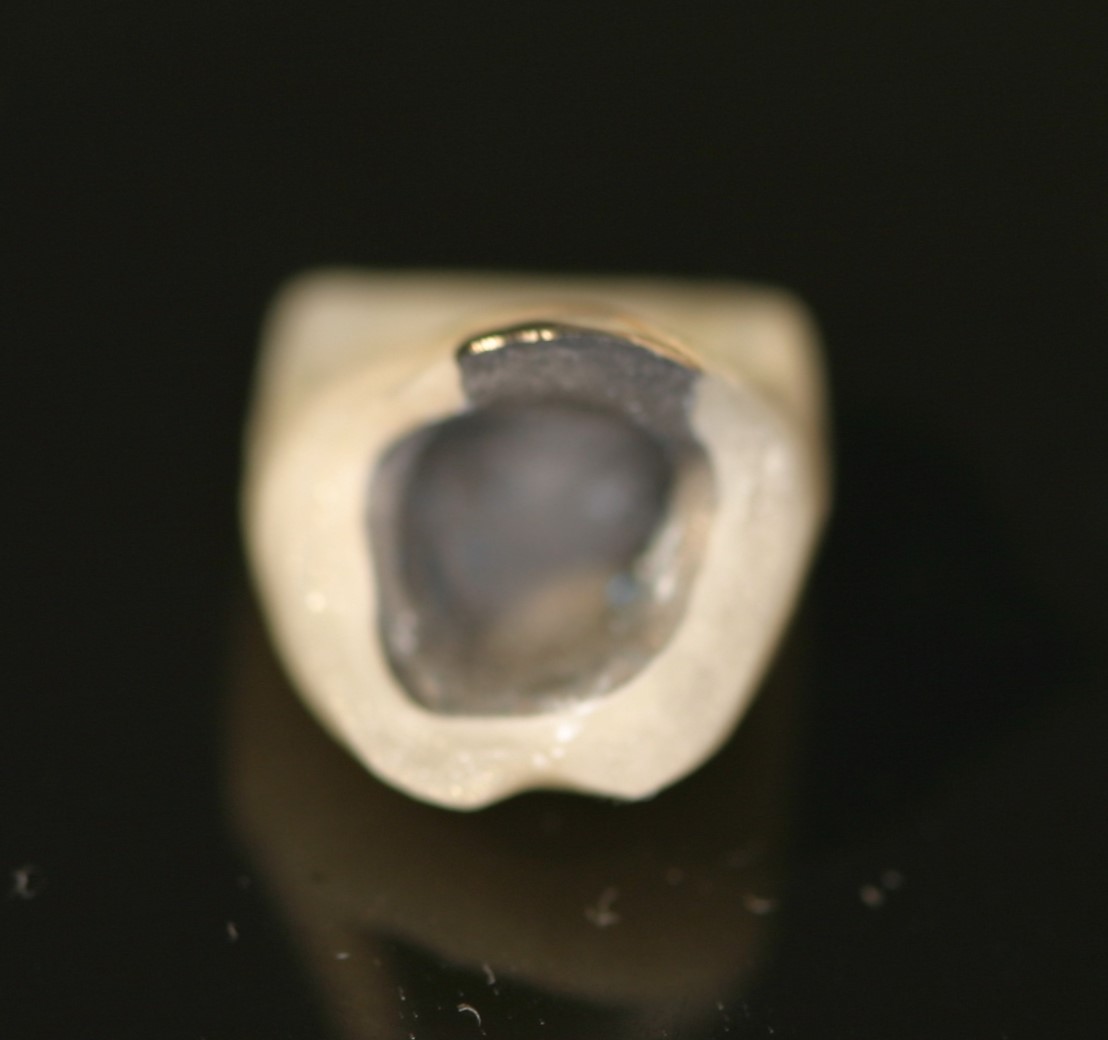

Custom made crown to allow cleaning of the defective tooth: